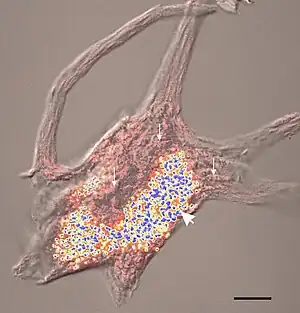

| Confocal image of a spinal motor neuron showing stained lipofuscin granules in blue and yellow. | |

Neuronal ceroid lipofuscinosis is the general name for a family of at least eight genetically separate neurodegenerative lysosomal storage diseases that result from excessive accumulation of lipopigments (lipofuscin) in the body's tissues.[2] These lipopigments are made up of fats and proteins. Their name comes from the word stem "lipo-", which is a variation on lipid, and from the term "pigment", used because the substances take on a greenish-yellow color when viewed under an ultraviolet light microscope. These lipofuscin materials build up in neuronal cells and many organs, including the liver, spleen, myocardium, and kidneys.